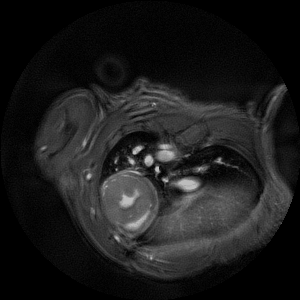

The ultra-high field of the BioSpec 152/11 provides extreme sensitivity for greatest resolution. Its streamlined design for mice studies makes handling simple, while its powerful software guarantees best results. It can be equipped with the MRI CryoProbe to increase sensitivity even further and together with the gradient strength of up to 1000 mT/m, highest resolution is achieved. It is built with nitrogen-free Ultra Shielded and helium Refrigerated (US/R) magnet technology for long service intervals

• Crisp and highly resolved images with native gradient strength of 740 mT/m, upgradable to 1000 mT/m

• MRI CryoProbe for exceptional increase in sensitivity